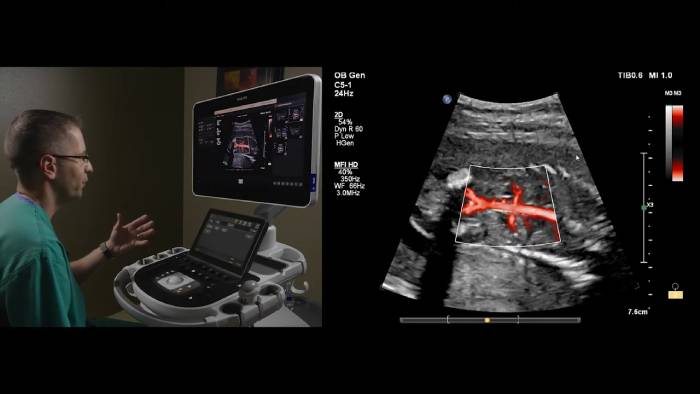

The EPIQ Elite system delivers exceptional frame rates, uniformity and penetration, with powerful features like Flow Viewer for 3D-like rendering of flow imaging data to help better visualize fetal vessels and fetal heart structures, MicroFlow Imaging High Definition (MFI-HD) to detect low-volume, low-velocity blood flow found in fetal, placental, uterine and ovarian vasculature, and TrueVue Pro 3D for photorealistic fetal images. Next Gen AutoScan reduces button pushes for greater efficiency.